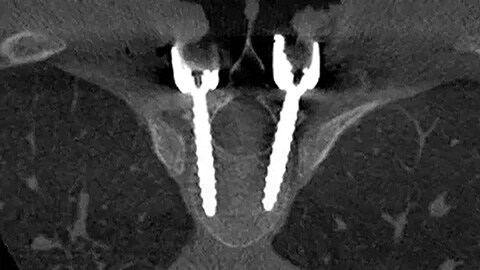

Предоставляет более подробное представление об анатомии позвоночника для проведения точного планирования и успешной установки импланта.